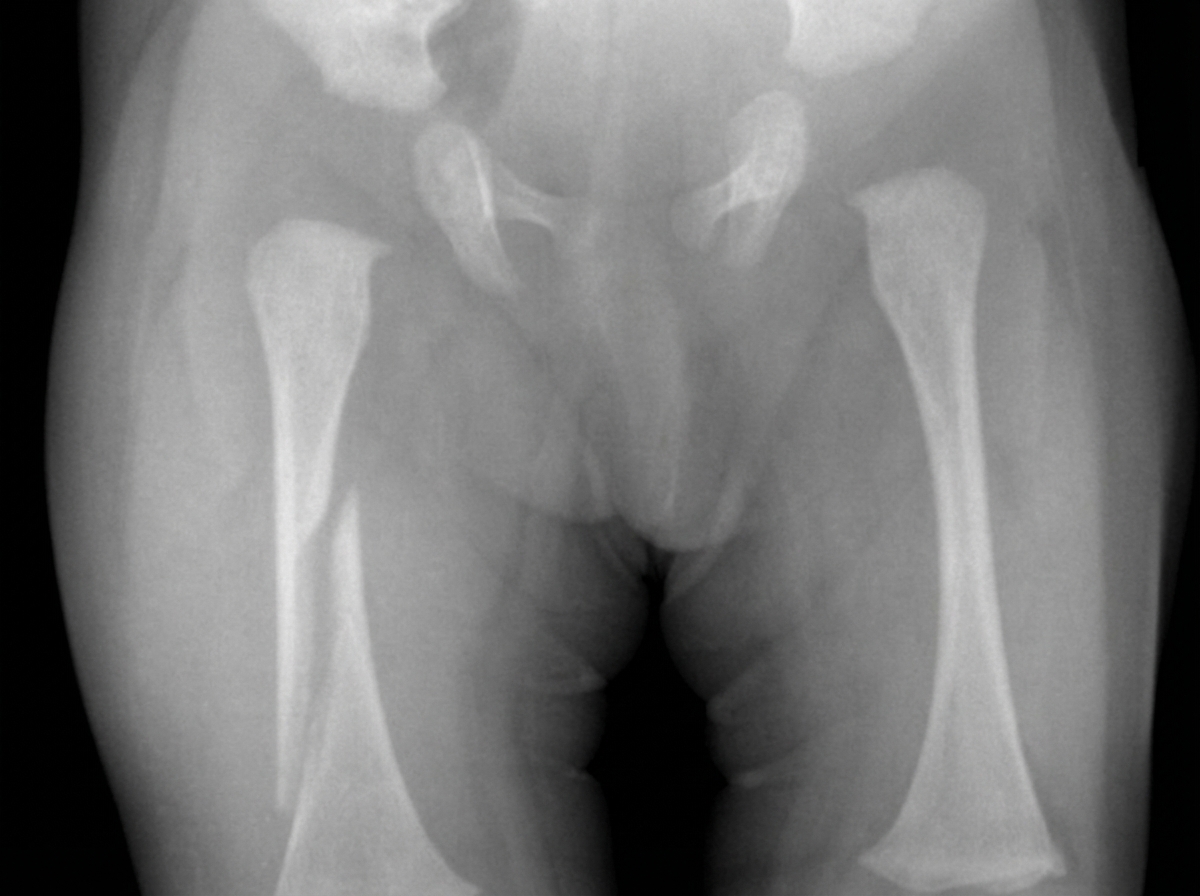

Explanation: ***Upper third of shaft*** - The **upper third of the femoral shaft** is anatomically defined as the proximal portion between the **lesser trochanter** and the junction with the middle third. - Fractures here are significant due to **deforming muscle forces** - the **iliopsoas** and **gluteal muscles** cause **flexion and abduction** of the proximal fragment, making reduction challenging. *Middle third of shaft* - This region lies between the upper and lower thirds, roughly at the **mid-diaphysis** of the femur. - While common for femoral shaft fractures, it lacks the specific **anatomical landmarks** and **muscle deformity patterns** characteristic of upper third fractures. *Lower third of shaft* - Located in the **distal diaphysis**, approaching the **supracondylar region** near the knee joint. - Fractures here may involve the **gastrocnemius muscle** causing **posterior angulation** of the distal fragment, different from upper third mechanics. *Neck region* - Refers to the **femoral neck** between the **femoral head** and **intertrochanteric region**, not the shaft. - **Femoral neck fractures** have different classification systems (**Garden classification**) and are typically **intracapsular** with risk of **avascular necrosis**.

Explanation: **Explanation:** The **Vascular Sign of Narath** is a clinical finding specifically associated with **congenital or traumatic posterior dislocation of the hip**. **1. Why Dislocation of the Hip is correct:** In a normal hip, the head of the femur lies directly behind the femoral artery in the groin, providing a solid "floor" or resistance. When the femoral head is dislocated (typically posteriorly), this bony support is lost. Consequently, when a clinician palpates the femoral artery in the femoral triangle, the pulsations feel significantly **diminished or hollow** because the artery has "sunken" into the empty acetabular space. This phenomenon is Narath’s sign. **2. Why other options are incorrect:** * **Dislocation of the Knee:** While vascular assessment is critical here (due to potential Popliteal artery injury), it does not involve Narath’s sign, which is specific to the femoral head/acetabulum relationship. * **Dislocation of the Elbow:** Associated with Brachial artery injuries (especially in supracondylar fractures), but not Narath’s sign. * **Dislocation of the Shoulder:** May involve Axillary artery or nerve injuries, but the anatomical "hollow" sign described by Narath is unique to the hip. **3. Clinical Pearls for NEET-PG:** * **Posterior Dislocation (Most Common):** Presents with a limb that is **Shortened, Adducted, and Internally Rotated**. * **Anterior Dislocation:** Presents with a limb that is **Abducted and Externally Rotated**. * **Associated Nerve Injury:** The **Sciatic nerve** (specifically the peroneal division) is most commonly injured in posterior hip dislocations. * **Emergency Status:** Hip dislocation is an orthopedic emergency due to the high risk of **Avascular Necrosis (AVN)** of the femoral head.